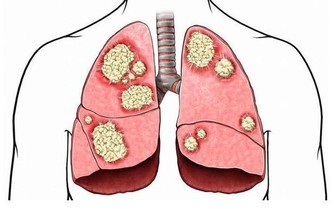

3.阿爾茨海默病的晚期症狀(8-12年)

• 患者完全依賴照護者生存;

• 嚴重的記憶力喪失,僅存片段的記憶;

• 大小便失禁,呈現緘默、肢體僵直,日常生活不能自理;

• 有強握、摸索和吸吮等原始反射。

最終昏迷,一般死於感染等並發症。